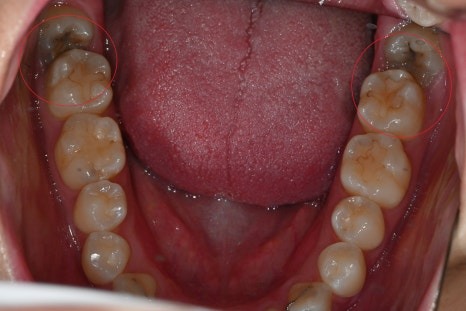

수면 충치치료 실제 케이스

치료 전

치료 후

· 60대 남성 환자

기존 보철물 주변 충치와 다수의 어금니 손상으로 내원

→ 수면치료를 통해 하루에

충치치료와 임플란트 수술까지 병행

크라운 치료 전

크라운 치료 후

· 20대 여성 환자

치과 공포증으로 치료를 미루다 충치 진행

→ 수면으로 양측 어금니 크라운 치료 및

매복 사랑니 발치 동시 진행